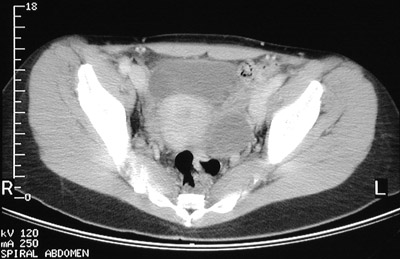

| In this pelvic CT scan can be seen cystic enlargement of the left ovary. This is an endometrioma, or focus of endometriosis involving the ovary in which repeated hemorrhage has led to formation of a cystic structure. The uterus and the urinary bladder are seen clearly. |